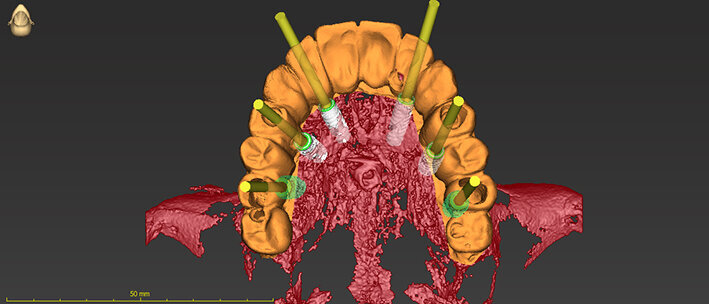

Nei casi di atrofie marcate, è fondamentale ricostruire l’osso mancante ma anche poter dare all’arcata una forma ideale. In questo caso clinico la paziente si presenta alla mia osservazione con una marcata atrofia del mascellare superiore (Fig. 1). La valutazione clinica è stata effettuata con esami radiografici di routine, OPM ed endorali, ma soprattutto con una Cone Beam TC. Da alcuni anni infatti, effettuo tutte le valutazioni diagnostiche in ambiente CAD con un software di chirurgia computer guidata che consente di valutare l’osso residuo in relazione al posizionamento tridimensionale dell’impianto protesicamente guidato.

L’approccio è quello di duplicare la protesi mobile utilizzata quotidianamente dalla paziente per renderla, attraverso punti di repere radiopachi, protesi radiologica. La paziente eseguirà la Cone Beam con la protesi radiologica e grazie alla presenza dei punti di repere radiopachi si potrà fare il matching tra i dati DICOM e la protesi della paziente (Figg. 2-4). Durante questa prima valutazione risulta evidente l’assenza di osso attorno agli impianti. La marcata perdita ossea è prevalentemente orizzontale e si estende in senso antero-posteriore su tutta l’arcata mascellare. Nella zona degli incisivi il posizionamento protesicamente guidato non è possibile a causa dell’assenza orizzontale dell’osso. Nelle zone posteriori inoltre si evidenziano i prolassi dei seni mascellari che riducono ulteriormente la disponibilità ossea. Di fronte a un quadro clinico così complesso si rende necessaria una scelta oculata della tecnica ricostruttiva adeguata.

Stabilita la tecnica rigenerativa è necessario fare delle valutazioni sul periodo post operatorio e quindi sul tipo di protesi provvisoria da far indossare alla paziente. Escludendo tutte le tipologie di protesi mobili per almeno sei mesi (compresa quindi una protesi sostenuta da un impianto posizionato nel palato), sempre con l’ausilio del software di chirurgia guidata ho quindi ipotizzato l’inserimento di due impianti nella zona della tuberosità (Fig. 5). Con l’ausilio della dima chirurgica sono stati inseriti tre impianti, due nelle tuberosità mascellari e uno nel palato (Fig. 6). Sui tre impianti è stato progettato insieme ai tecnici un dispositivo in metallo che potesse sostenere dei denti fissi non rimovibili (Fig. 7). Il risultato ottenuto è stato eccellente perché la paziente ha portato una protesi fissa fin dal giorno dell’intervento per tutto il periodo di guarigione, di circa nove mesi. La progettazione della ricostruzione ossea è stata quindi fatta in maniera Protesicamente Guidata, sono stati posizionati gli impianti virtuali e poi valutata l’entità della rigenerazione necessaria.

Una volta ottenute tutte le informazioni necessarie dei dati ossei (Cone Beam), della pianificazione protesica (STL della ceratura, dei tessuti e della situazione iniziale) l’azienda (ReOss, Filderstadt, Germany) invia il progetto della griglia Yxoss CBR che può essere visualizzato in maniera tridimensionale ed eventualmente modificato a discrezione del professionista. Suggerite le eventuali modifiche si esegue la validazione finale del progetto per la realizzazione della griglia (Fig. 8).Con la Customized Bone Regeneration (CBR) l’obiettivo della Rigenerazione Protesicamente Guidata in senso digitale viene così raggiunto. Le griglie sono prodotte attraverso una stampa tridimensionale e il loro fit al difetto è sempre accuratissimo consentendo di concentrare l’attenzione alle altre fasi dell’intervento.